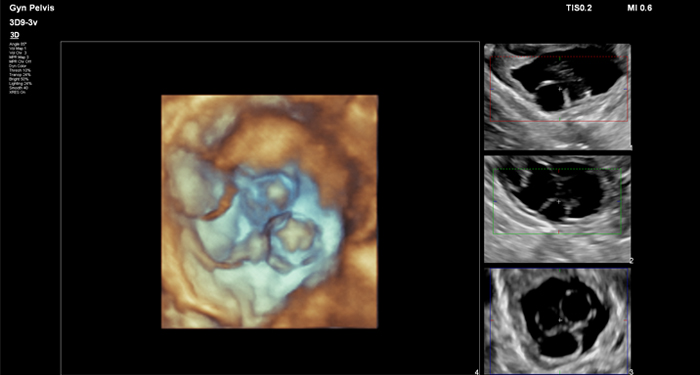

At the touch of a button, the new MaxVue high-definition display brings extraordinary visualisation of anatomy with 1,179,648 additional image pixels compared to a standard 4:3 display format mode. MaxVue enhances ultrasound viewing during interventional procedures and provides 38% more viewing area to optimise the display of dual, side/side, biplane, and scrolling imaging modes.

MaxVue offers a 38% greater viewing area.

MaxVue offers 1,179,648 additional image pixels compared to a standard 4:3 display format mode.